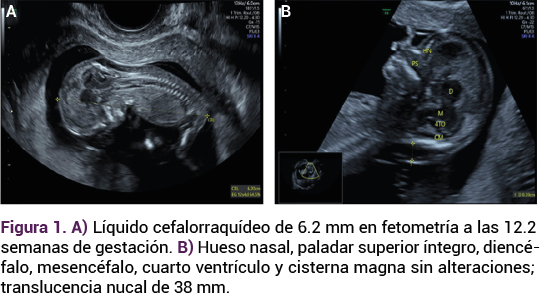

Paciente de 32 años, con antecedente de dos embarazos y una cesárea, indicada por macrosomía fetal, el actual en curso de las 13.3 semanas, por fecha de la última menstruación, con dos consultas de control prenatal, consumo de multivitamínicos, sin infecciones urinarias y vaginales. Sin recuerdo de problemas patológicos. El ultrasonido del primer trimestre reportó: feto único vivo, con frecuencia cardiaca de 163 lpm, con movimientos, placenta anterior corporal, inserción central del cordón umbilical, bolsillo mayor de líquido amniótico de 3.43 cm, longitud craneocaudal (LCC) de 6.20 mm para 12.2 semanas de gestación; translucencia nucal de 39 mm (Figura 1). La ecografía Doppler: IP de ductus venoso de 1.23, IP de arterias uterina derecha e izquierda 0.81 y 1.20, respectivamente. Anatomía fetal, situs solitus, burbuja gástrica, riñones y vejiga sin alteraciones demostrables lo mismo que la anatomía cardiaca.

<strong>Figura 1</strong>

Figura 1.